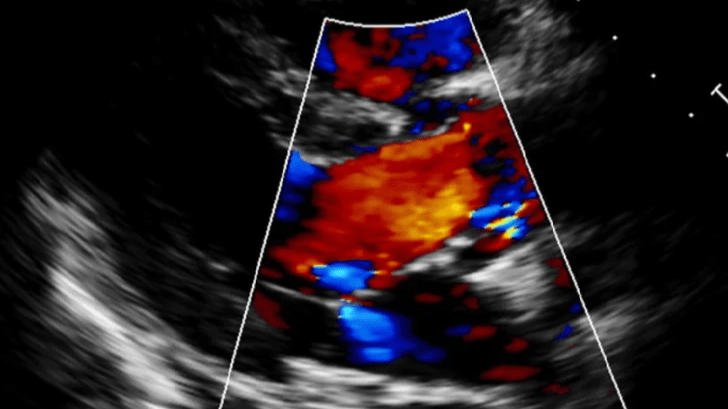

心血管門診

不只喘咳、有時突然昏迷、抽搐也是心血管問題,術前評估心臟功能也很重要!

整合X光與彩色督卜勒超音波,針對心臟腔室,血液動力學做出完整測量提供最準確、有效的心臟病治療方案,有效控制心臟衰竭,同時提供手術病患麻醉前的心臟評估,手術更安全,老年動物也能放心接受手術治療,得到更好的生活品質。